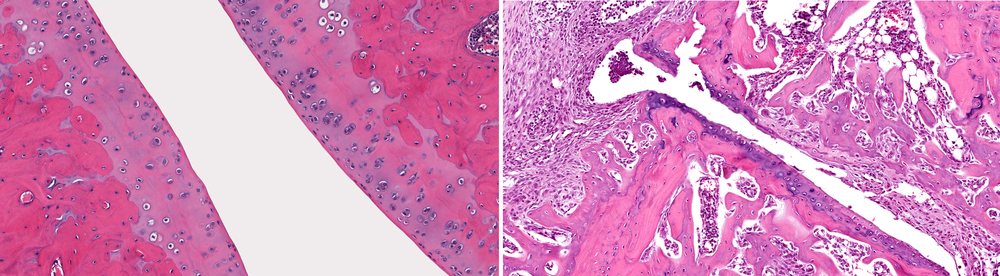

[Microscopic view of normal healthy joint (left) when compared to joint with osteoarthritis with loss of articular cartilage, fibrosis, inflammation and loss of bone (right)]

The surface of joints is covered with articular cartilage—a smooth bearing surface with a dense matrix, few cells, and no blood vessels. When injured by a fall or a sports injury, the dent in the articular cartilage never heals. If the injury is large enough to both expose the underlying bone and cause bleeding, a degree of healing can occur. But the repair tissue is usually not the same as the normal cartilage. When the healing is inadequate, pain recurs.